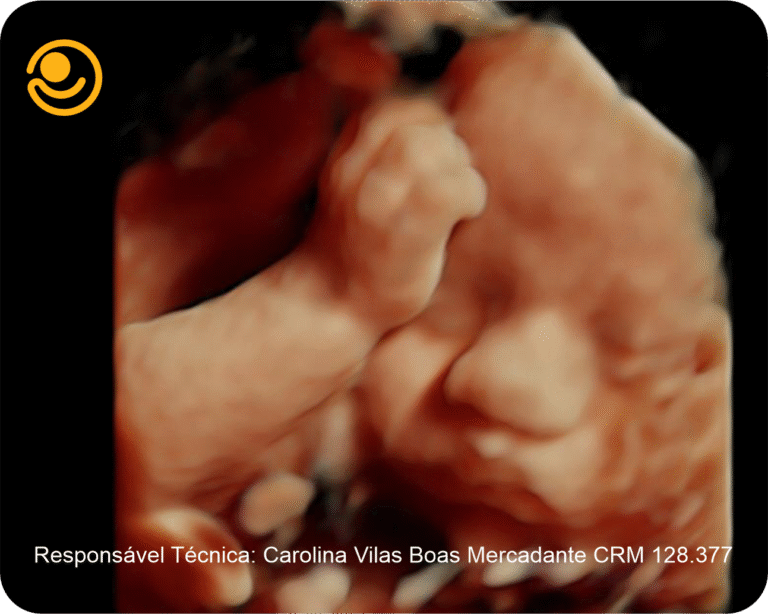

Imagens 3D / 4D

✓ Ultrassonografia 3D/ 4D com imagem em HD